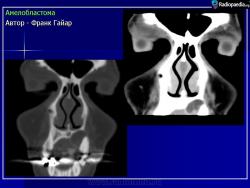

Амелобластома

ID: 9430 Ameloblastoma Dr Frank Gaillard - 16 Apr 2010 Ameloblastoma resected en-blocAuthor: Berto1286Original files:http:...

ID: 3992 Ameloblastoma - maxillary Dr Frank Gaillard - 7 Jul 2008 CT through the maxilla obtained with contrast demonstrates a cystic lesi...